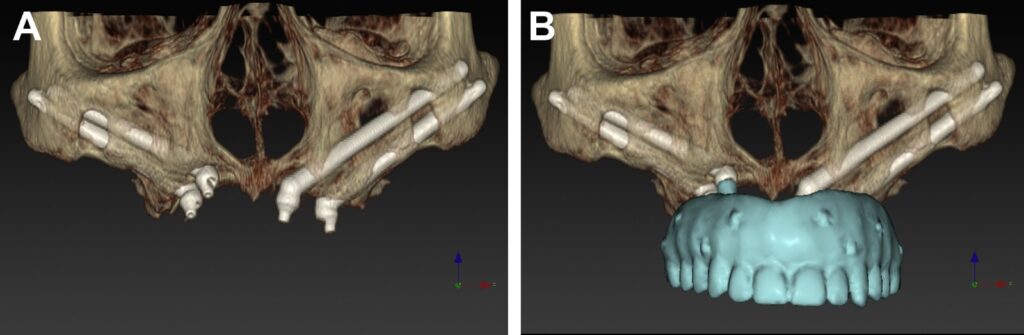

Elevate your dental care journey with our membership program, specifically designed for patients seeking teeth implants. As a member, you’ll benefit from reduced pricing on implant procedures, priority scheduling for consultations and treatments, and continuous follow-up care to ensure the best outcomes. Join today to access top-tier dental implant services and enhance your smile with confidence.